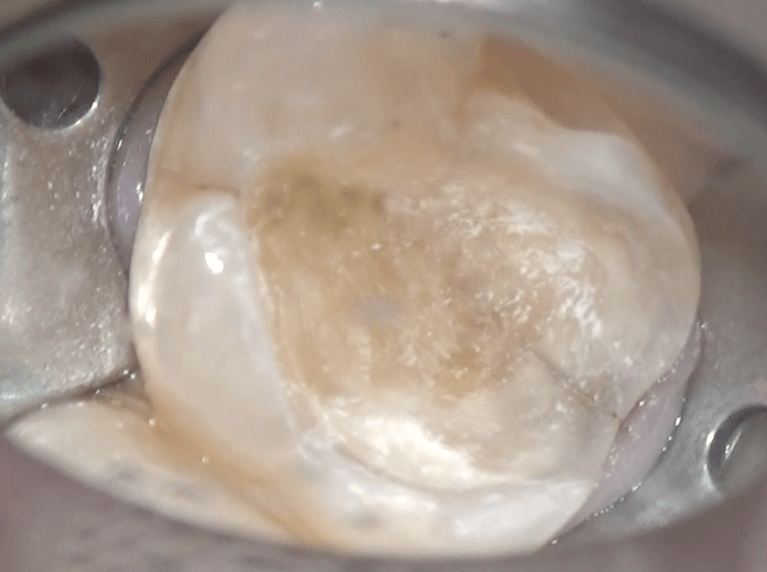

きれいになったところです。この上に

コンポジットレジンで土台を作り、本日は終了になります。